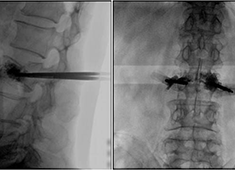

C臂機在打骨水泥時是怎么使用的(PKP手術(shù)記錄)

在打骨水泥時通常要借助C臂機來進行,具體是如何使用的呢?下面通過南京醫(yī)科大學第二附屬醫(yī)院的一則手術(shù)案例來深入學習。首先將患者處于俯臥位,然后利用普愛大平板C臂機擺位靈活的特點,快速定位椎弓根位置...